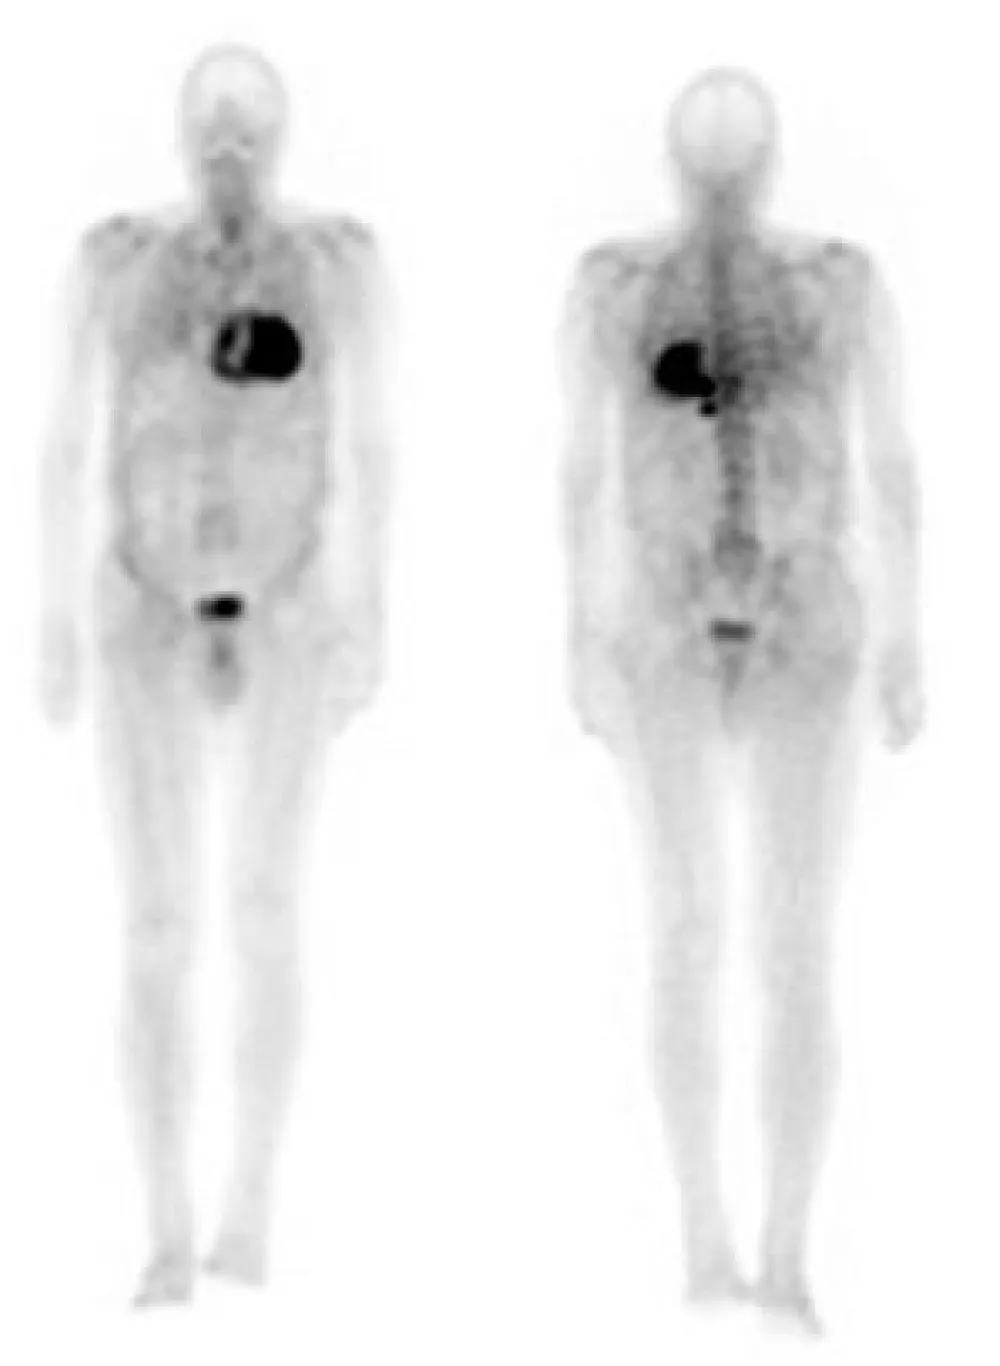

In order to identify the origin of amyloidosis, a Tc99m-DPD scan was requested, after obtaining written patient informed consent, a planar whole-body scintigraphy was performed 2 hours after intravenous injection of 740 MBq, that showed intense biventricular myocardial tracer uptake grade 3 (greater than the bone uptake), compatible with cardiac TTR amyloidosis, (Figures 1,2). Finally, a Genetic Testing resulted negative for TTR gene Mutation, which is consistent with the diagnosis of cardiac amyloidosis ATTRwt.

Figure 1: Anterior and posterior views whole body 99mTc-DPD scan. Marked myocardial uptake, suggesting an amyloid infiltration.